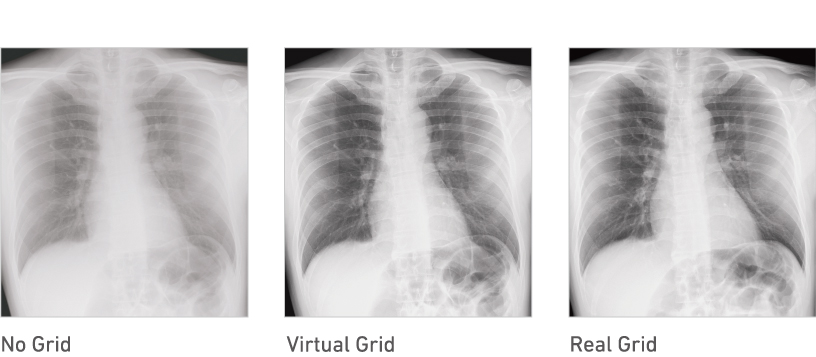

Virtual Grid processing corrects for the effects of scatter radiation. Without the need for a grid, Virtual Grid retains high contrast and image sharpness, while preventing the asymmetric density resulting from misalignment of X-ray tube and detector.*5